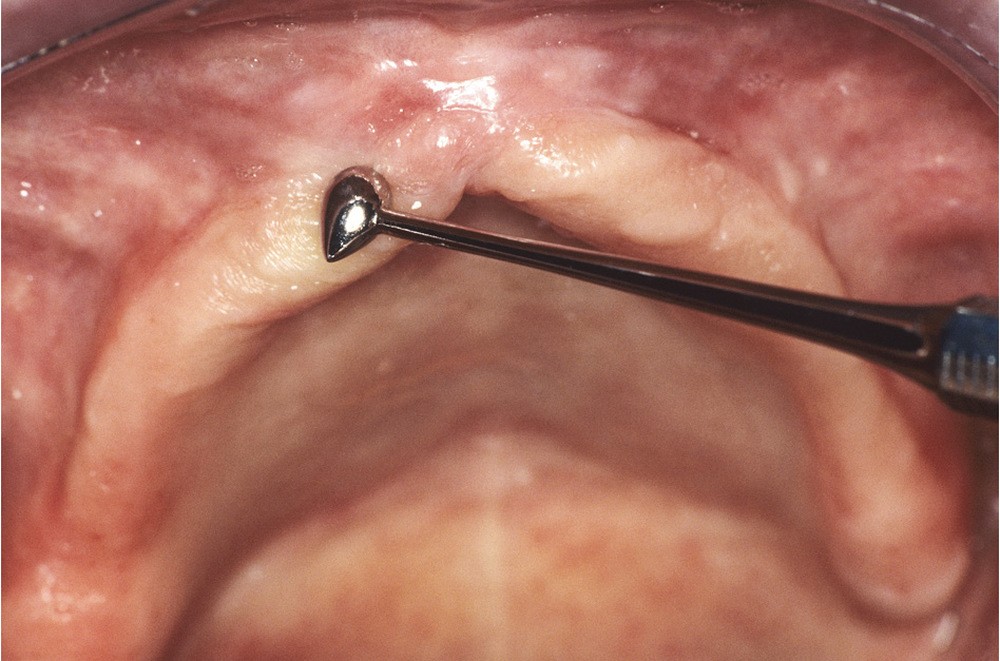

Ainsi, la chirurgie préprothétique a pour objectif de corriger les anomalies congénitales ou acquises des tissus durs et des tissus mous supports d’une prothèse amovible afin d’établir des conditions anatomiques favorables à une réalisation prothétique de qualité [6]. L’objectif de cet article est de présenter les indications et les techniques chirurgicales préprothétiques sur les tissus mous.

Un bilan préopératoire complet est indispensable pour évaluer les risques médico-chirurgicaux. Les contre-indications absolues ou relatives liées à l’état de santé du patient sont globalement celles de la chirurgie orale, avec cependant la spécificité de la prise en charge des patients âgés [6]. Au niveau des tissus mous…